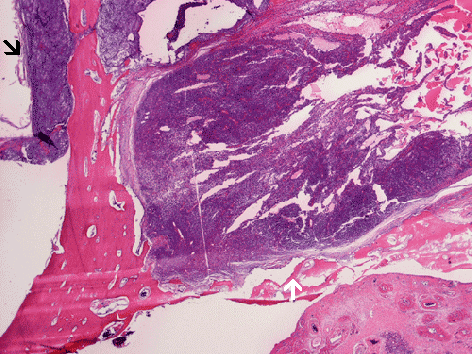

The two images on the left are sagittal sections of the decalcified maxillectomy specimen. The white arrow points to the location where the hard palate is invaded. The black and white arrows locate the areas with bone invasion and corresponding locations are shown in the histologic image on the right.